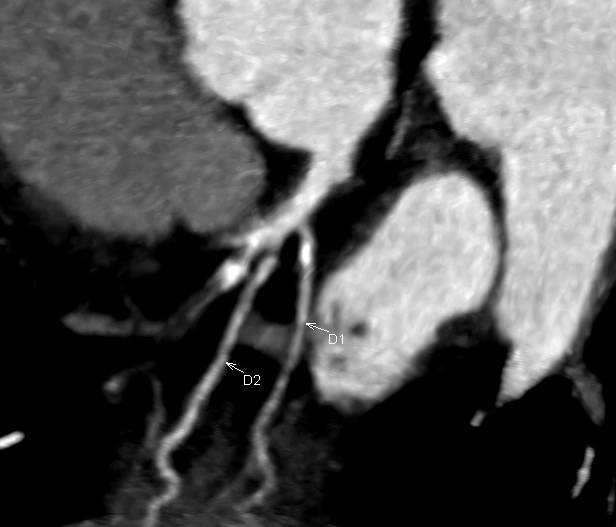

Cardiac CT

CARDIAC CT. Explained.